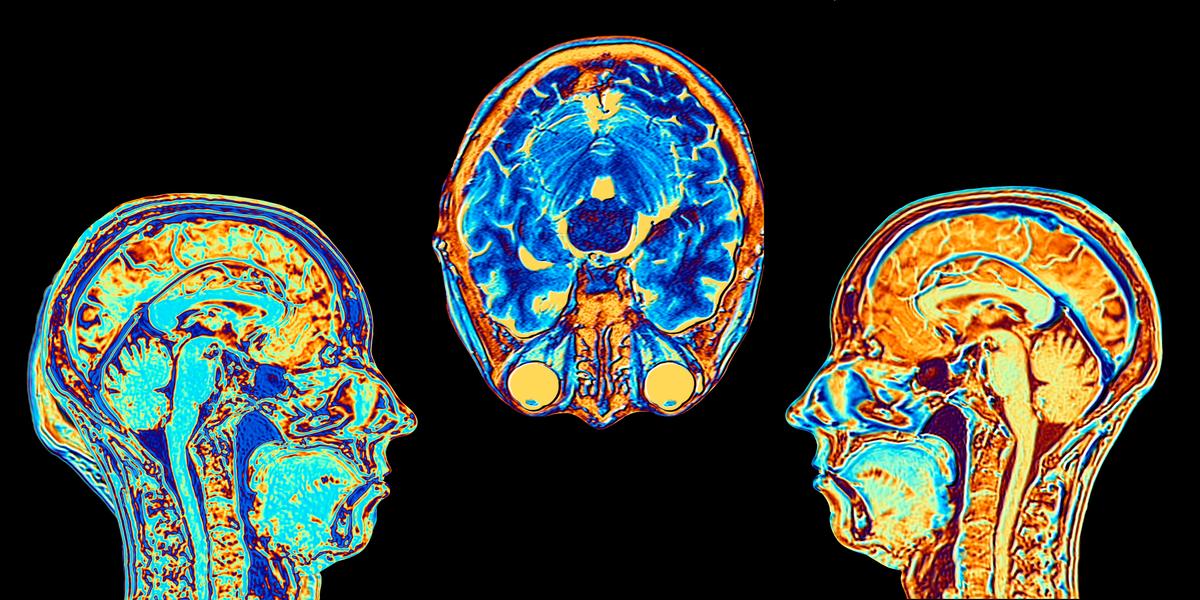

The U.S. Food and Drug Administration (FDA) has approved Voranigo, a new drug from the French pharmaceutical firm Servier, for the treatment of a type of brain cancer.

It is the first treatment in the United States to be approved by the FDA for treating a form of brain cancer, called Grade 2 IDH-mutant glioma, in patients who have had surgery.